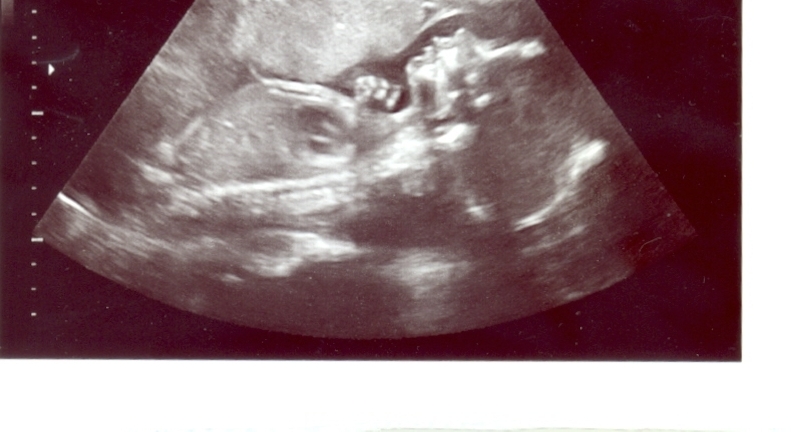

-Finally…there is the picture of my baby-boy-to-be.  Every time I look at the photo, I smile.  We have a real little person in there.  He has a little profile (that looks strikingly similar to The Prince’s profile) and a little hand.  You can even see his heart in the photo!  (It’s the shaded area in the chest).  I can’t fathom having him taken away.  And I don’t mean just that I am afraid of him being taken away (which is more akin to my usual use of the phrase “I can’t fathom”).  I mean that I truly can’t imagine or comprehend a scenario where I don’t get to see that little profile in person, staring up at me as I feed him.  I’m really happy and content holding onto that visual right now…and I hope this photo keeps me going for the next 15 weeks.

UPDATE ON THE BABY

Dr. B had told me the baby was small.  Not so.  At yesterday’s ultrasound, the baby measured in at 1.1 pounds…putting him in the 78th percentile for weight.  He is over a foot long.  Everything looked great, structurally speaking.  My placenta is “in front,” which the nurse said would likely lead to me not feeling strong movements and would mean I wouldn’t feel the baby move as early in the pregnancy as most women (wrong and wrong).  The baby is in a head down posiiton, against my pubic bone.  Dr. C isn’t worried about the position.  While it isn’t comfortable, it isn’t indicative of the baby coming out too soon.  We didn’t get any cute 3D shots of the face, although Dr. C and the ultrasound tech tried really hard.  There is a sufficient amount of amniotic fluid in the sac, but not much of it in front of the baby’s face.  We did get a great profile shot, in normal black and white.  I will probably post it later on…but I’ll give a warning in case people want to avoid it.

During the scan, Dr. C did a close-up on the baby’s ears.  They stick out…just like The Prince’s did before his surgery.  The Prince is adamant that, if our baby has “stick out” ears (we’re not talking a little…The Prince’s were almost straight out on the side of his head), we will have surgery done when he is still a baby.  It was too traumatic for The Prince as an adult, and The Prince’s doctor told him that it would have been much easier to fix when he was a baby and the cartilage was still soft.  I pray we don’t have to make that decision.  Dr. C said all babies have big ears at 22 weeks…but I’m skeptical.  Still…no matter what his ears look like, our baby is really beautiful.  I know I’m biased…but his features really looked adorable on the scan.